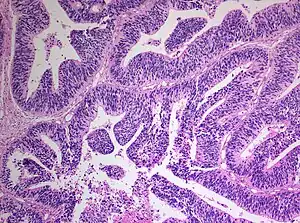

| Histopathology of medulloepithelioma showing characteristic neural tube like strands. | |

a)Papillary and tubular patterns represent the distinctive appearance of medulloepithelioma b)positivity of the neoplastic cells for S100 protein c) PanCytokeratin

Histologically, medulloepithelioma resemble a primitive neural tube and with neuronal, glial and mesenchymal elements.[8][9] Flexner-Wintersteiner rosettes may also be observed.[10]